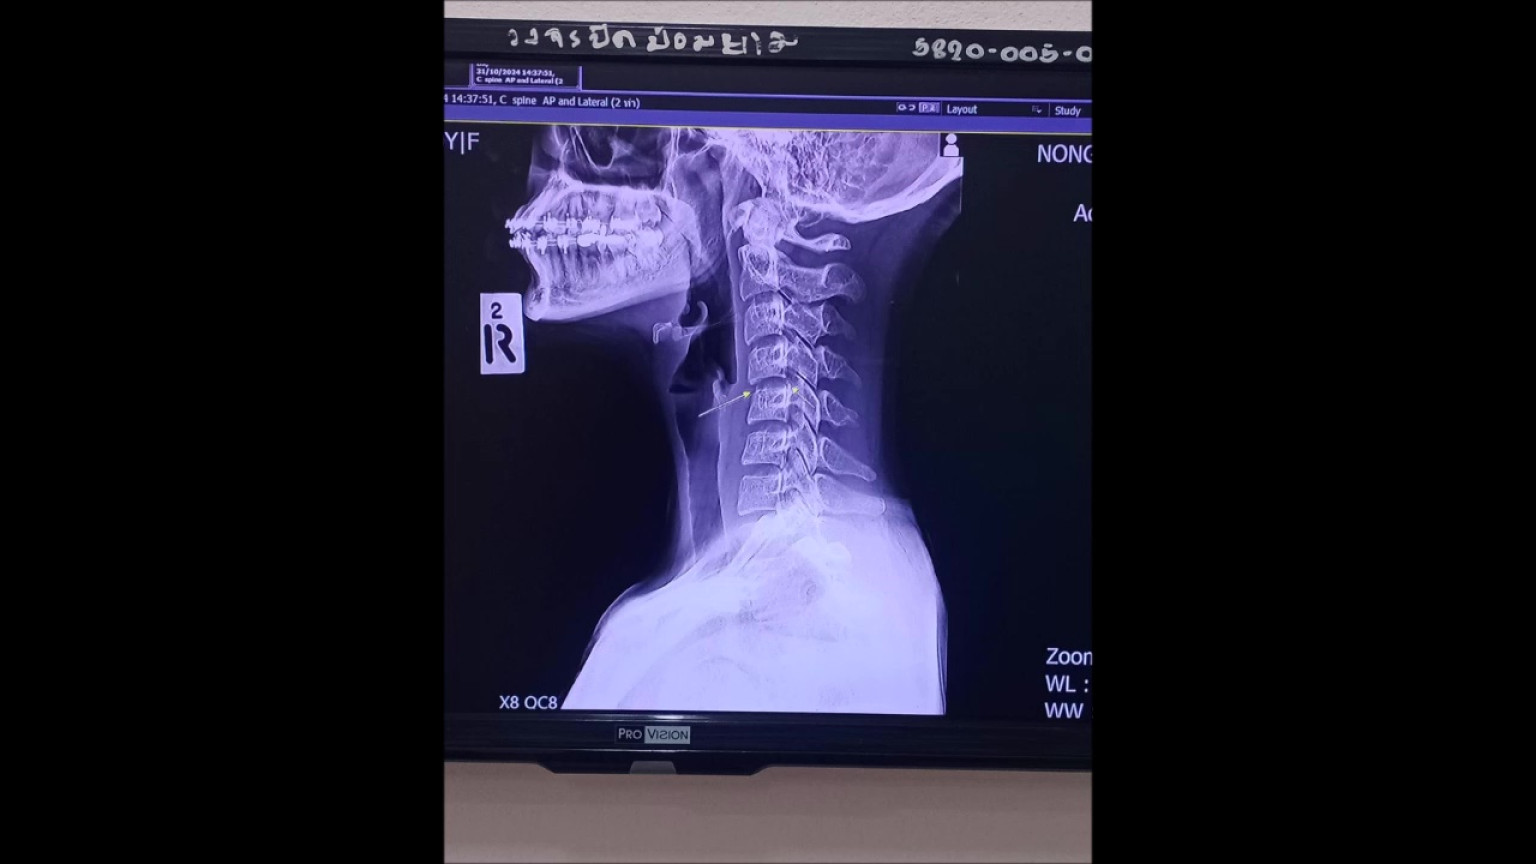

วันที่ 8 ธ.ค.67ผู้สื่อข่าวรายงานว่า จากกรณีเพจเฟสบุ๊ก ผิง ชญาดา นักร้องสาวรถแห่ ได้โพสต์รูปภาพเอกซเรย์ พร้อมระบุข้อความว่า ไม่รู้จะเริ่มยังไงดี คนทักถามเยอะมากว่าเป็นอะไร คืองี้หนูไปนวดที่ๆหนึ่งมาค่ะ ในอุดร อาการตอนก่อนไปนวดคือหนูปวดแค่ไหล่เฉยๆค่ะ หนูไปนวดครั้งแรกอาการตอนนวดเสร็จปกติค่ะ ผ่านมา2วันหนูเริ่มปวดท้ายทอย หนูนึกว่าเป็นอาการปวดของการนวดปกติ มีการบิดคอ หลังจากนั้นหนูกินยาระงับอาการค่ะผ่านไปอีก1สัปดาห์หนูเริ่มมีอาการชาลงแขนค่ะ ไปนวดอีกหมอคนเดิมห้องเดิม รอบนี้ (บิดคอ)อีกนะคะ ผ่านไป2สัปดาห์หนูเริ่มปวดตึงมากๆมากๆค่ะจนนอนหงายคว่ำไม่ได้แต่แม่หนูเป็นหมอนวดหนูเรียนนวดมาตั้งแต่เด็กๆค่ะ หนูชอบนวดมาก หนูยังไม่เอะใจอะไรค่ะนึกว่าเป็นเอฟเฟคจากการนวดอีก (ปวดตัวแบบนี้) หนูไปอีกค่ะ ห้องเดิม เบอร์เดิม แต่เป็นคนใหม่คนนี้นวดแรงบวมช้ำอยู่เป็นสัปดาห์(ไม่ใช่คนที่บิดคอนะคะ) มีล้วงใต้ราวนม (จั๊กแร้)ค่ะ หลังจากนั้นหนูกินยาเพื่อบรรเทาอาการมาตลอดค่ะ เริ่มมีอาการไฟซ๊อตไปปลายนิ้วค่ะ คันมากจนอยากตัดมือทิ้ง ร้อนๆหนาวๆตลอดเวลาค่ะ ก้มแล้วร้าวลงขา ซีกขวารู้ว่าตัวเองชาก็ตอนทาโคโลนหลังจากรอบที่3ที่ไปนวดค่ะ เริ่มรามไปท้อง ราวนม อาการชาเริ่มมากขึ้นเรื่อยๆค่ะ ผ่านไปอีก2อาทิตย์แขนขวาหนูเริ่มยกไม่ได้ค่ะ(อ่อนแรง) จนถึงตอนนี้ร่างกายหนู ใช้งานได้ไม่ถึง50%ค่ะ หนูมาเล่าเพราะมีคนถามมาเยอะ อยากฝากไว้เป็นอุทาหรณ์สำหรับใครที่ชอบนวดมากๆนะคะ หนูจะต้องหายค่ะ หนูทรมานมาก อยากทำงานแล้วค่ะ แต่ตอนนี้รอแค่เวลา ขอบคุณที่อ่านจนจบ

โดยโพสต์ดังกล่าวมีมีคนมาแสดงความเห็นและแชร์ออกไปจำนวนมาก ซึ่งคอมเมนต์แสดงความห่วงใยและเสียใจหลังทราบข่าวว่าน้องผิง นักร้องสาวรถแห่เสียชีวิตเมื่อเช้าวันนี้ (8 ธ.ค.67) ที่รพ.ศูนย์อุดรธานี หลังจากต้องทนทุกข์ทรมานจากการนวดต้นคอและป่วยติดเตียงมาเกือบ 2 เดือน และบางคอมเม้นบอกว่าอาจเกิดจากกระดูกเคลื่อนทับเส้นประสาทและมีอาการแทรกซ้อนอื่นๆ สมองบวม